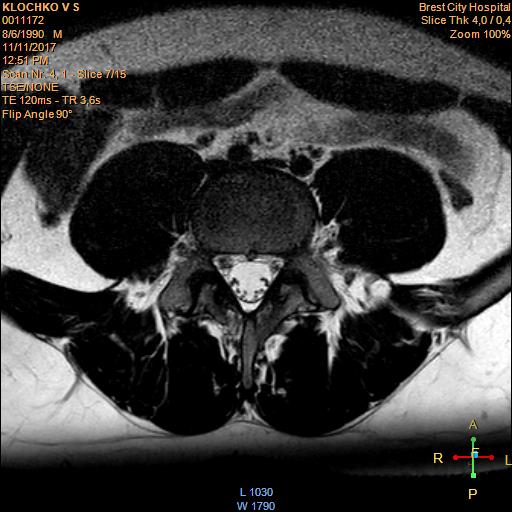

Тренировки с межпозвоночной грыжей.